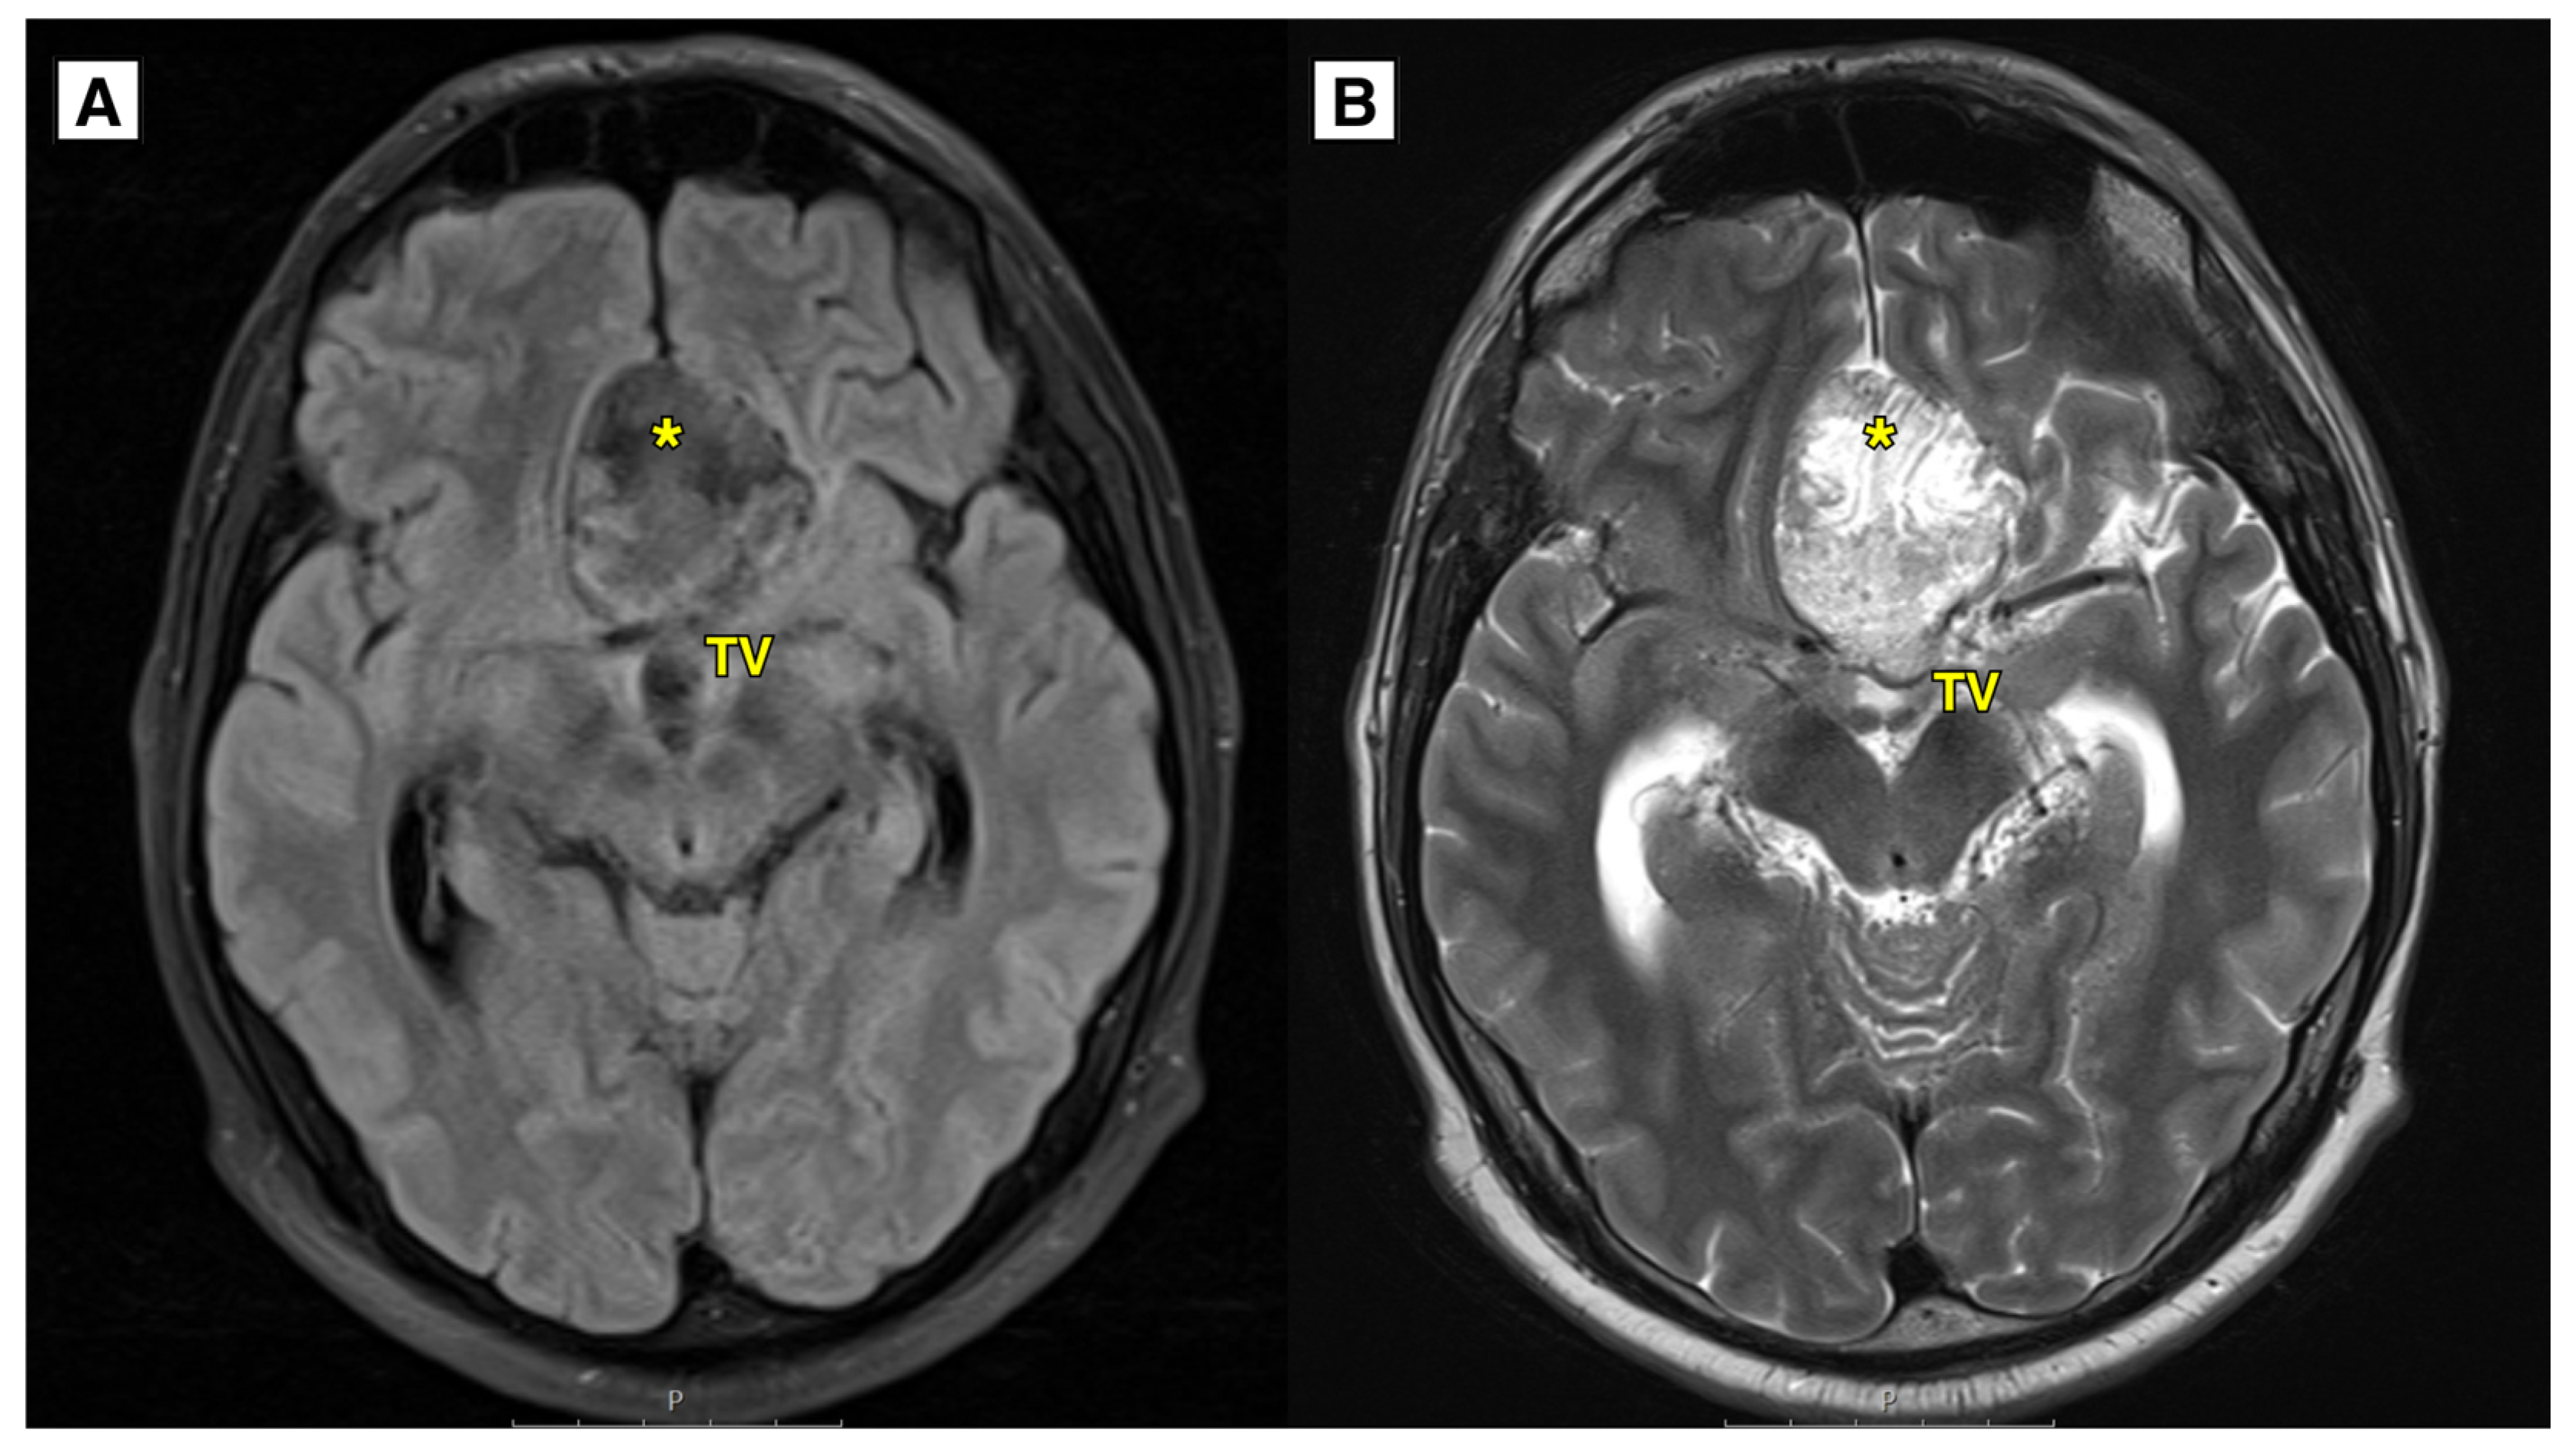

A: MRI of the brain (T2-FLAIR axial sequence) showed a slightly hyperintense lesion, most likely a dermoid cyst, located in the basal dorsal anterior fossa. The cyst extended into the suprasellar cisterns, positioned above the chiasma opticum and the prechiasmal part of the optic nerve. It was situated under the anterior cerebral arteries and caused compression and displacement of the anterior parts of the third ventricle. Despite this, the foramen of Monro remained open. Additionally, there was an expansion of the lateral and third ventricles. B: MRI of the brain (T2W-TSE axial sequence) showed an intracranial cyst located in the anterior fossa. The lateral ventricles were dilated with the temporal horns measuring up to 8.5 mm, indicative of hydrocephalus. The likely cause of hydrocephalus development was a combination of the ruptured dermoid cyst and its intraventricular spread, exerting mass effect on the third ventricle and aqueductus cerebri. TV – third ventricle, * – intracranial dermoid cyst.

An MRI brain scan was performed on an outpatient basis. MRI revealed most likely a ruptured dermoid cyst located in the anterior fossa, with mass effect on the optic chiasm, prechiasmatic part (

Figure 1 and

Figure 2). Dermoid cyst dimensions: 4.6 x 4.0 x 2.5 cm (AP x LL x CC) (

Figure 1). Susceptibility weighted imaging (SWI) sequence showed hypointensity with blooming artifact (